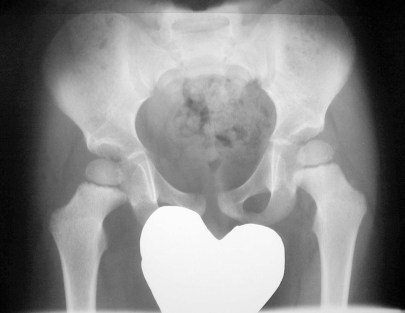

SIGNO DEL BORDE

Engrosamiento de la línea ileopectínea vista en la radiografía de pelvis, que corresponde a la afectación de este hueso en la enfermedad de Paget. Este signo, que corresponde a reacción osteoblástica en la zona, está presente en la mayoría de pacientes con enfermedad de Paget pélvica.